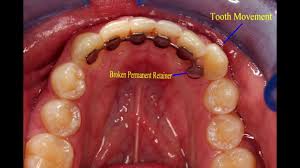

Dental Appliances Can Prevent Your Teeth From Shifting After Orthodontic Treatment Orthodontist Brisbane

Dental Appliances Can Prevent Your Teeth From Shifting After Orthodontic Treatment Orthodontist Brisbane from orthodontistbrisbane.net